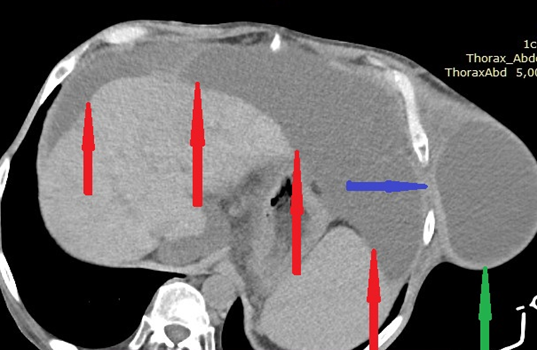

CT άνω κοιλίας με σκιαγραφικό που αναδεικνύει συστάδα διατεταμένων ελίκων λεπτού εντέρου στο κέντρο δίνοντας εικόνα κουνουπιδιού (βέλη) (Ευγενική παραχώρηση Dr. V. Penopoulos)